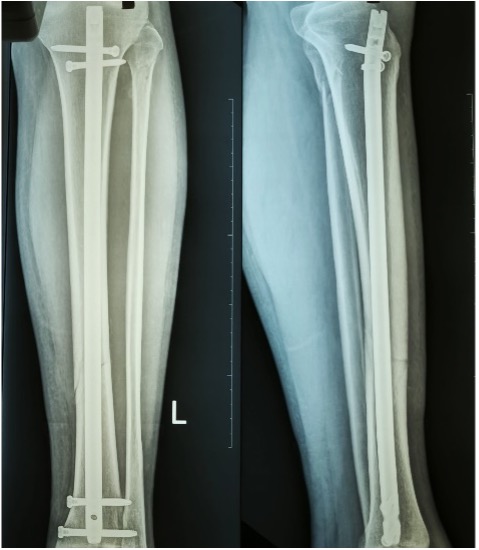

| Ακτινογραφική απεικόνιση τρεις εβδομάδες μετά την έναρξη των θεραπειών. |

Η τελευταία φάση της αποκατάστασης οποιουδήποτε τραυματισμού του κάτω άκρου περιλαμβάνει πάντοτε την αποκατάσταση της ισορροπίας και της ιδιοδεκτικότητας, καθώς αυτές είναι απαραίτητες για την λειτουργικότητα και την αποφυγή μελλοντικών τραυματισμών.